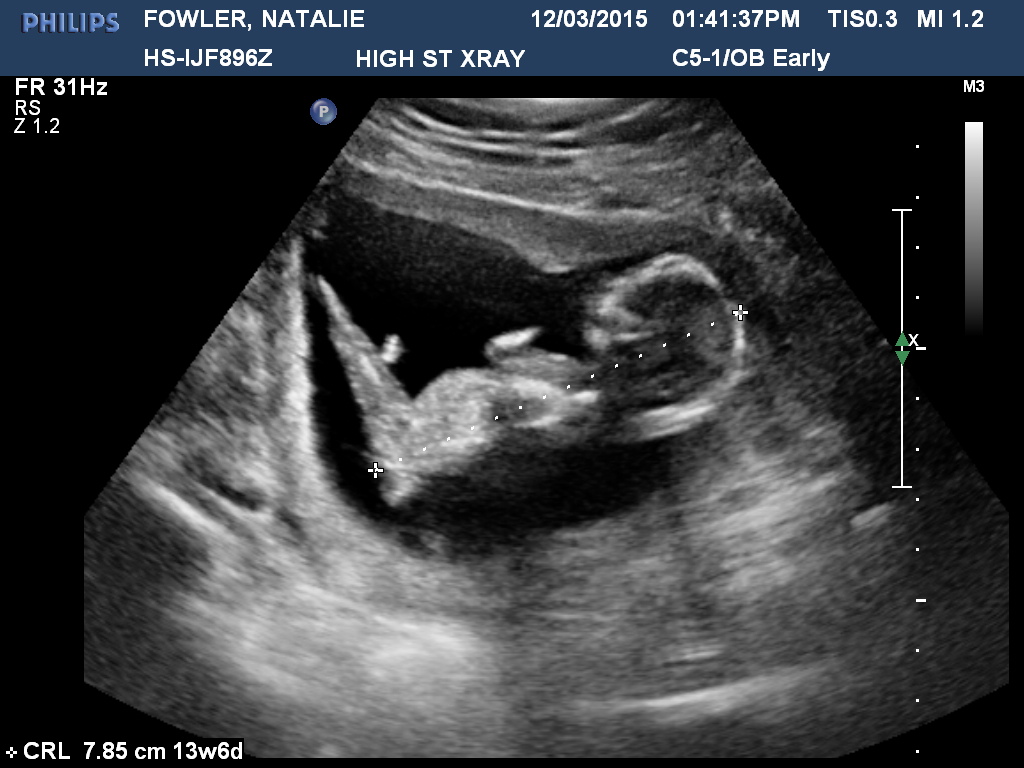

The longer I look at this scan, the more confused I get! Baby is measuring at 13w6d, any ideas would be amazing :)

youve got a lot of cord going on but id give it a boy lean

It's a tricky one. I had a nub just like that (confirmed girl) in one of my shots and it looks boy at first but because of how the baby is almost sitting upright it's just a weird angle so I'm guessing girl

Leaning girl

I think the nub is a bit higher. Careful boy lean. Lots going on doen there